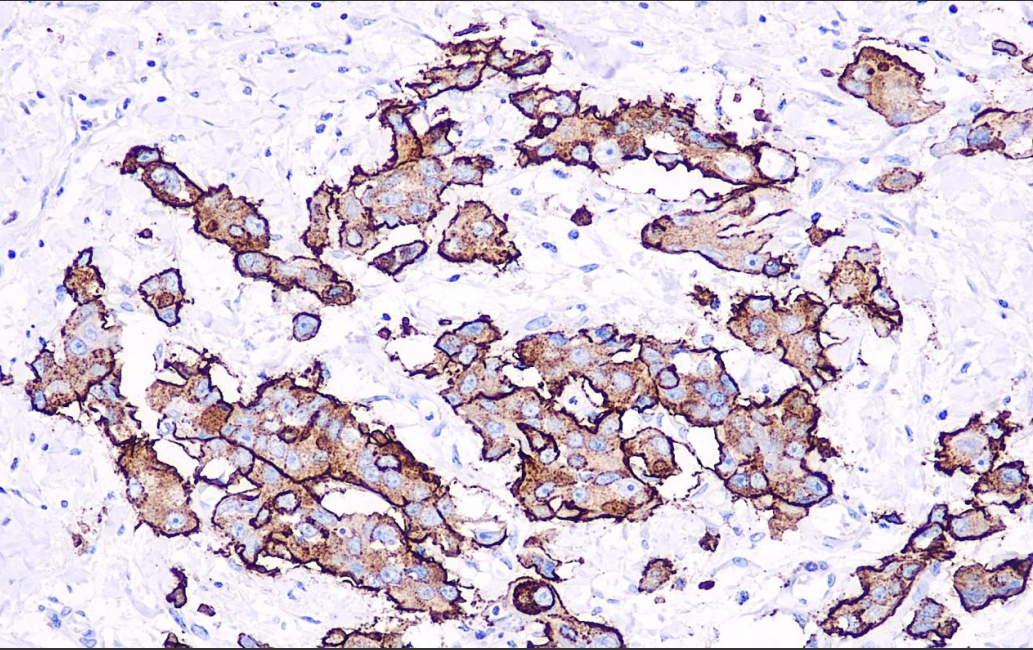

Positive control: Breast cancer

CA15-3 antigen is a mucin-like glycoprotein with a molecular weight of 300-450 kDa, and its expression is closely related to the degree of differentiation and estrogen receptor status of breast cancer. It is important for the study of breast cancer and metastatic breast cancer, and can be used as one of the reference bases for breast cancer research, as well as for the study of other malignant tumors (e.g. lung cancer, ovarian cancer).

CA15-3 Antibody Reagent binds specifically to CA15-3 molecular antigen. Immunohistochemistry kits containing CA15-3 Antibody Reagent are suitable for the precise diagnosis of breast, lung, and ovarian cancer.